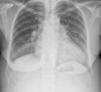

Initial clinical investigation included laboratory tests, which revealed anemia, negative D-dimers and myocardial necrosis markers, and elevated pro-BNP (Table 1), and the chest X-ray showed increased cardiothoracic index (Figure 2).

The findings from physical examination pointed towards hyperthyroidism and laboratory tests confirmed a diagnosis of GD. Various mechanisms lie behind the pathogenesis of PH in GD; unlike their effects at the peripheral level, thyroid hormones do not reduce pulmonary vascular resistance, and there is endothelial damage caused by the autoimmune process.9 We therefore interpret the clinical setting as PH secondary to GD, exacerbated by LV dysfunction caused by tachycardiomyopathy in the context of AF with rapid ventricular rate due to hyperthyroidism. Other common causes appear less likely, since there was no known history of pulmonary disease, the chest X-ray showed no relevant alterations, and there was no hypoxia, excluding ESC group 3 (PH due to pulmonary disease and/or hypoxia); negative D-dimers and low pre-test probability associated with resolution of the setting following antithyroid therapy make group 4 (PH due to thromboembolism) unlikely.